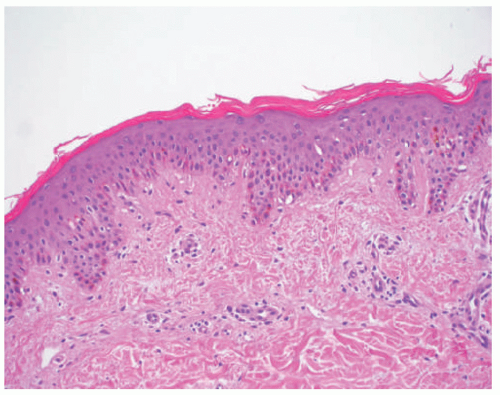

TABLE 7-2. Histopathologic findings for selected nonsyndromic ichthyoses | ||||||||||||||||||||||||||||||||

|---|---|---|---|---|---|---|---|---|---|---|---|---|---|---|---|---|---|---|---|---|---|---|---|---|---|---|---|---|---|---|---|---|

| ||||||||||||||||||||||||||||||||